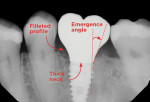

Type 3: A Shape Clinicians Can Love

The heart-shaped prosthesis is the third radiographic shortcut and the preferred shape (Figure 7). Its design will typically meet each desired criteria for success. Type 3 prostheses have a gentle emergence profile that is conducive to causing less stress and fewer complications.

To realize the full effect of this shape, the implant should be centered between two adjacent teeth. This minimizes cantilevers, reduces implant-to-tooth distance, and allows placement depth to be close to ideal for attractive esthetics results.10 With this design, occlusal loads are channeled directly to the implant, putting it under axial compression, which is widely viewed as the safest force that can be applied. Also, a type 3 solution permits use of a screw-retained crown, thereby eliminating the possibility of cement entering the sulcus. Furthermore, this approach significantly reduces costs associated with such cases because stock abutments may be used. With a type 3 radiograph, the chances of complications will be minimized, and the patient's long-term outlook will be excellent.

Remembering the three radiographic shapes discussed-Snoopy, E.T., and a heart-can aid the dental team in identifying possible risk factors associated with implants and help clinicians improve patient outcomes. Utilizing a type 3 prosthesis, with its gentle emergence profile, minimized cantilevers, and screw-retained solutions, can allow dentists to confidently provide patients with successful implant treatments that yield optimal esthetic results and long-term stability.